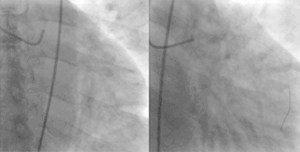

![]() A coronary angiogram showing the circulation in the left coronary artery and its branches. | |